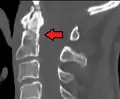

Fractures of the dens, not to be confused with Hangman's fractures, are classified into three categories according to the Anderson Alonso system:

- Type I fracture - Extends through the tip of the dens. This type is usually stable.

- Type II fracture - Extends through the base of the dens. It is the most commonly encountered fracture for this region of the axis. This type is unstable and has a high rate of non-union.

- Type III fracture - Extends through the vertebral body of the axis. This type can be stable or unstable and may require surgery.

A fracture of the base of the dens as seen on CT

Type 2 dens fracture